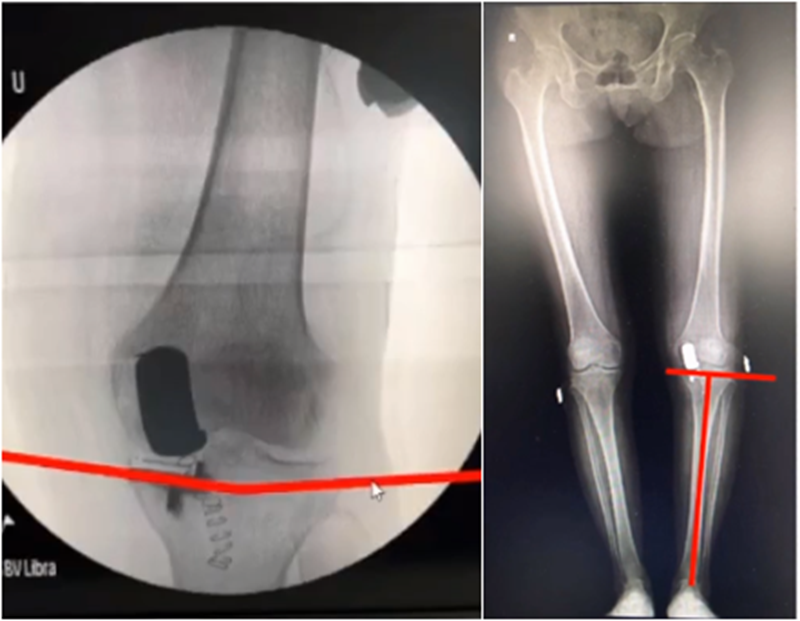

但实际术后需要通过全长片来判断是否能取得好的力线,判断有无过度矫正或矫正不足的情况出现。还需要通过全长片区分内翻畸形的来源在哪里,是否能矫正,对适应证的选择有一定帮助。如果术后下肢整体力线外翻3°,则说明外侧间室压力明显升高。

小结:对于下肢整体力线,首先保证术后力线不能外翻,术后力线内翻不能超过10°,而术前关节外畸形不能超过10°。

牛津单髁在假体评判中,提到股骨内外翻有10°容忍度,胫骨内外翻有5°,股骨屈伸在0-15°之间,胫骨后倾在 7-(﹣5)后倾之间。但评判标准中没有提到此种方式是基于全长片还是局部片。

文献中建议假体内外翻不大于4°,如果假体出现外翻,后倾大,会造成内侧皮质压力异常增高,增加内髁骨折风险。如果假体内翻超过5°,增加胫骨平台松动风险。

但有时候力线好,假体和外侧关节线会成角,那么对于此种情况,应如何判断假体位置内外翻定义?和外侧关节线比较,属于外翻假体;和下肢机械轴比较,属于中立位假体。

小结:判断股骨胫骨假体位置,是基于局部X线的判断,是考虑行走时关节线的方向为基准,此时内外翻不能超过5°,而不能从全长片来判断。